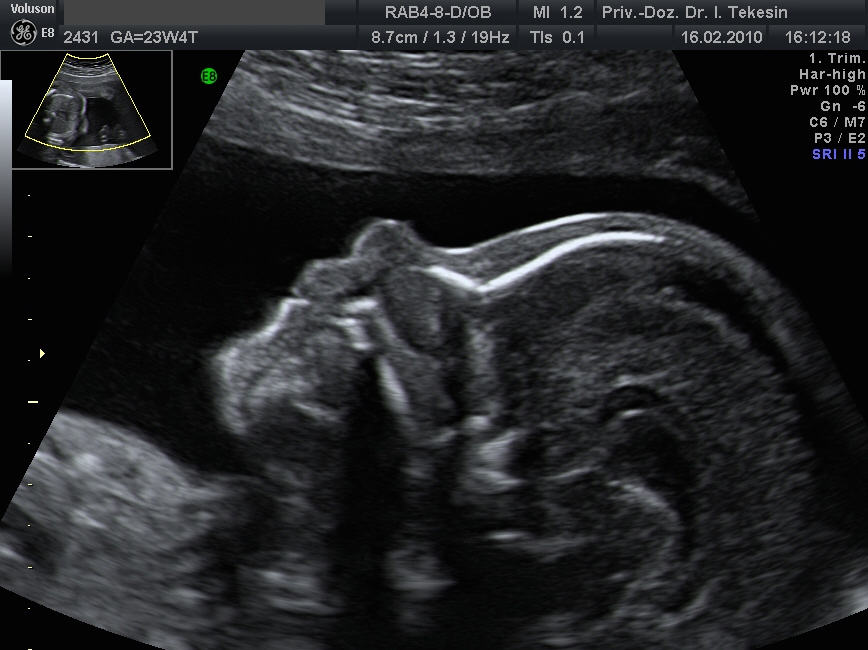

Frühe Fehlbildungsdiagnostik in der 13. SSW